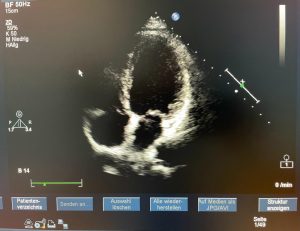

- Ultraschall des Herzens (Echokardiographie)

- Ultraschall unter Fahrrad-Ergometer-Belastung (Stressechokardiographie)